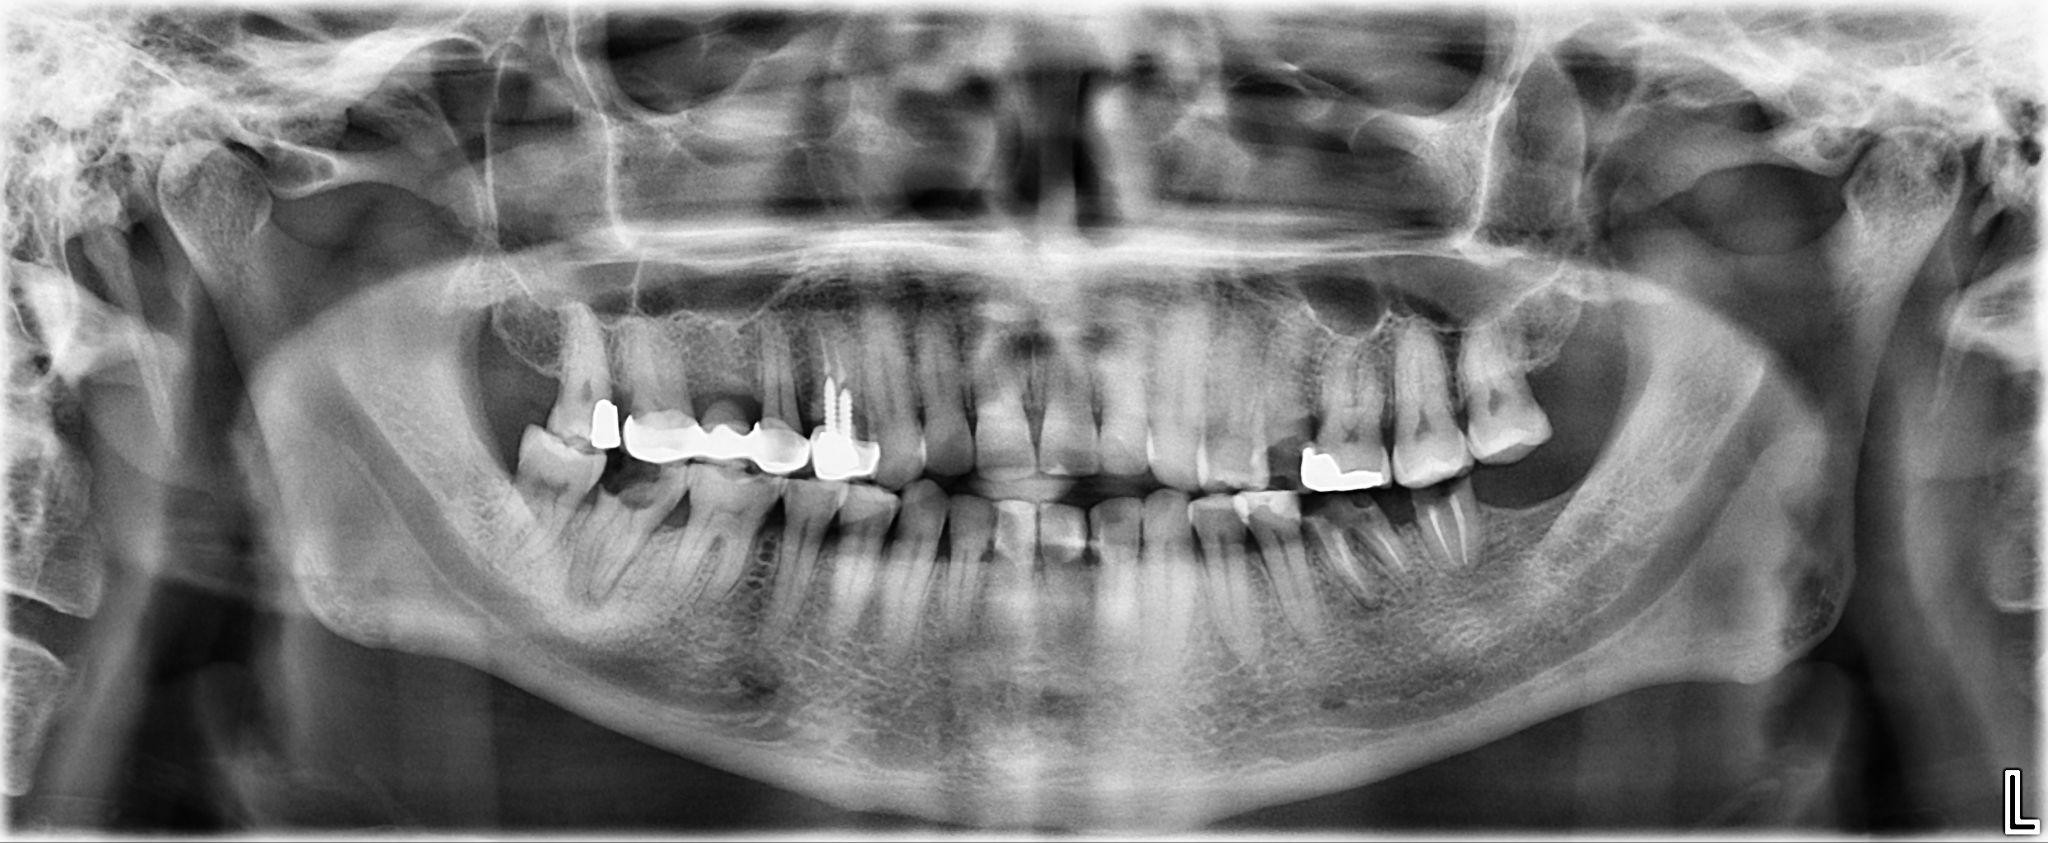

5 / 25

5. What option cannot be selected for the first quadrant of this panoramic X ray?

6 / 25

6. What option cannot be selected for the third quadrant of this panoramic X ray?

7 / 25

7. What option cannot be selected for the forth quadrant of this panoramic X ray?